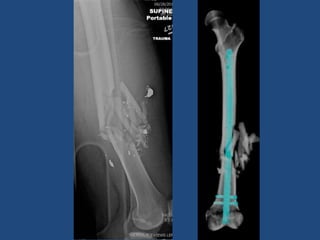

Femoral shaft and tibia fractures

nailing

• Typically patients may “WBAT” following

surgery